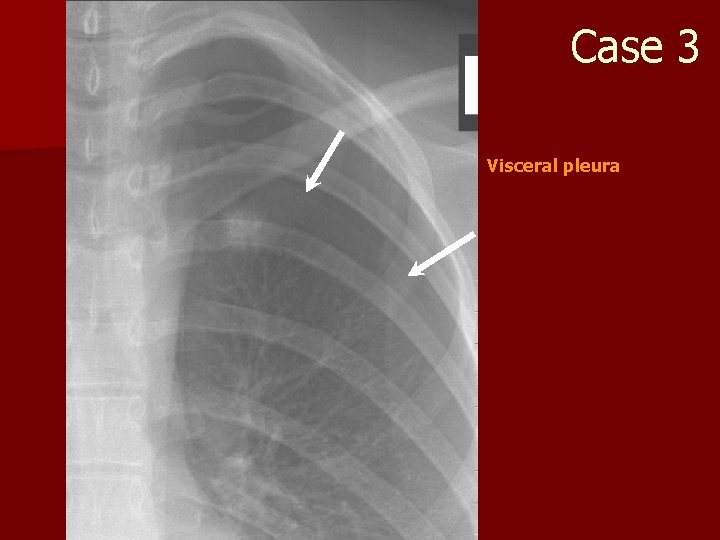

Case 3 Visceral pleura

Case 3 n Causes of pneumothorax? – Numerous! n Treatment? – Urgent – Chest tube – 25 G needle 2 nd intercostal space

Case 3 n Deep sulcus sign? – pneumothorax on supine films – especially seen in ICU patients